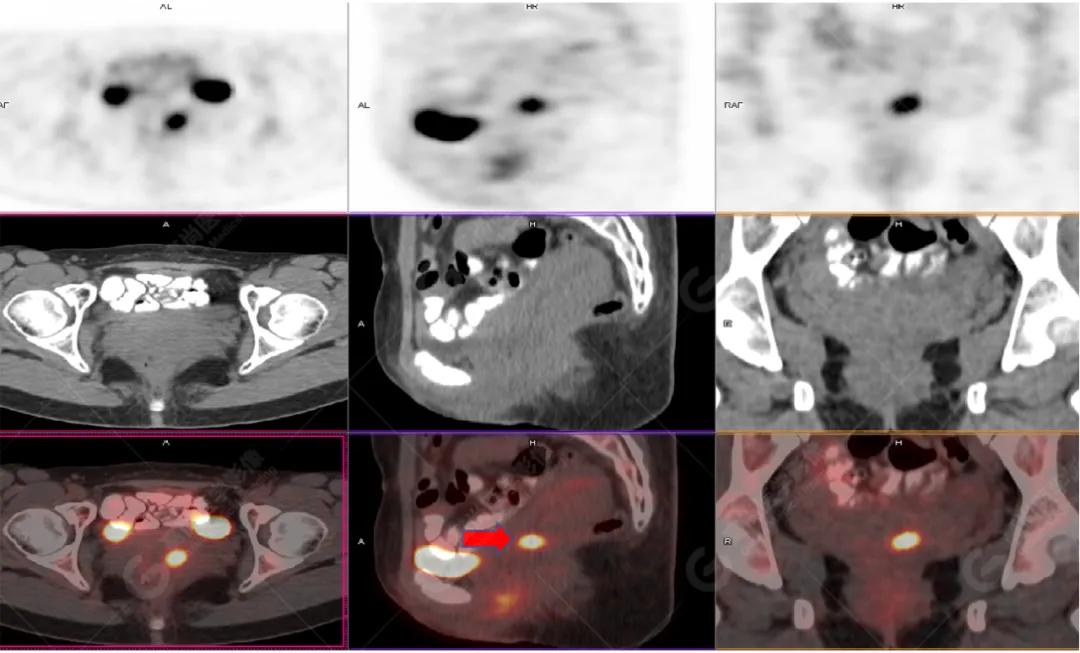

影像图

左胸一后肋溶骨性骨质破坏,周围伴软组织形成,FDG代谢增高,SUVmax为10.9。

找到引起骨痛病灶,病因:原发?转移?感染?

宫颈一片状稍低密度影,FDG结节样代谢增高,SUVmax为10.2。

最终诊断: 宫颈癌伴肋骨单发骨转移。